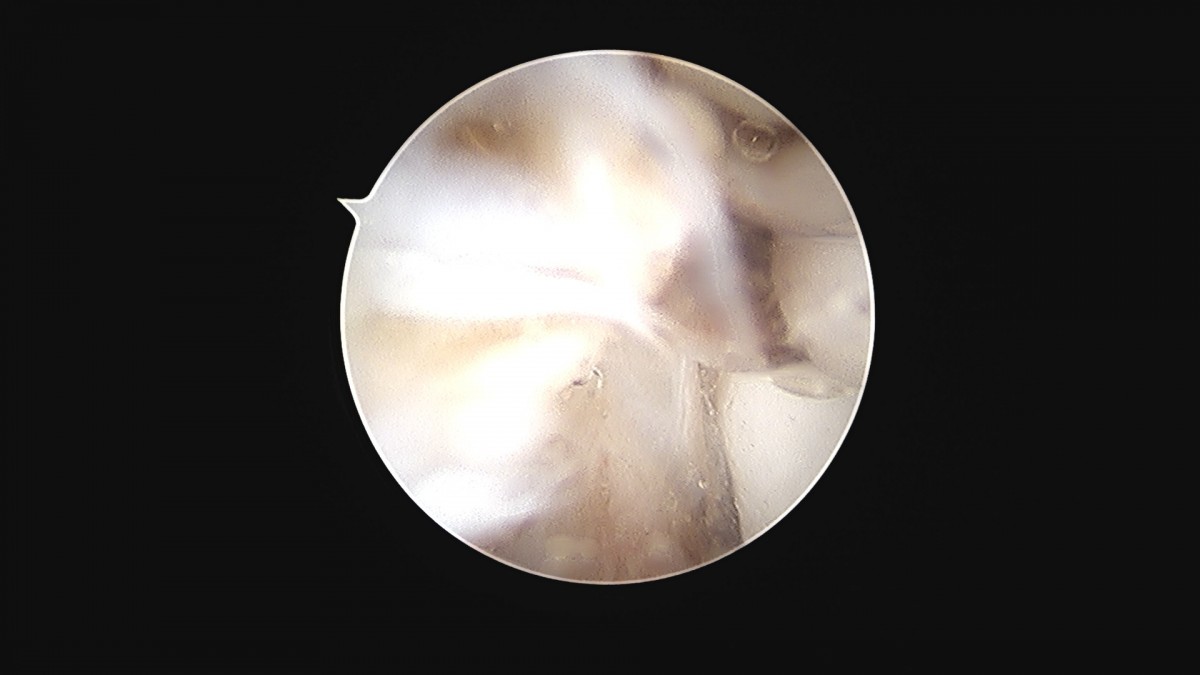

이재상원장님 발목 활액막 절제술 및 인대 봉합술 신진O 환자

dae765e4d9ac96aee867c9d6292d8784_1758003733_6364.jpg